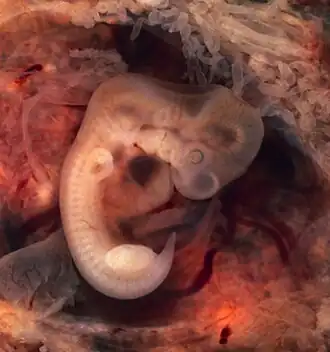

6 Weeks

- The length from crown to rump is about the size of a finger tip, ¾ ". The beginnings of all the major organs will have formed.

- The embryo floats in a fluid filled bubble that will develop into the amniotic sac. The sac is covered by a protective layer of cells, called chorion. The yolk sac supplies the embryo with all its nutrients until the placenta is fully developed and takes over at around the twelfth week. During the first 12 weeks, the embryo will develop features and major organs of a human being. The embryo is susceptible to harmful environmental influences. This is a vital time for the embryo to develop healthily; taking supplements of folic acid, avoiding certain foods, and eliminating alcohol, cigarettes, and any unnecessary drugs or medicines.

9 Weeks

- The length from crown to rump approximately 1 1/4". The facial features are becoming more distinct, and the “tail” has disappeared. The muscles are also developing. Eyes are formed but eyelids are still closed over them. Arms now bend at the elbow and rudimentary hands and fingers develop. Knees will have formed and developing feet with distinct toes.

- Heart- is now a four-chambered and fully formed organ; it beats about 180 times per minute.

- Brain and nervous system- is four times the size it was at 6 weeks. Special glial cells are being formed within the neural tube; they allow nerve cells to be joined so that messages can be transmitted from the brain to the body.

- Digestive system- the mouth, intestine, and stomach are developing very rapidly, but do not function yet.

- The fetal life-support system- the placental tissue that initially surrounds the fetus and the amniotic sac is becoming concentrated in one circular area on the womb wall to form the placenta.